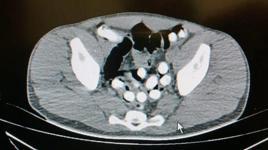

Ağrı’da bir yolcu otobüsünde polis ekipleri tarafından yapılan aramada İran uyruklu şahsın midesindeki şişliğin şüphe uyandırması üzerine yapılan incelemede mide ve bağırsaklarında uyuşturucu olduğu tespit edildi.

Ağrı Narkotik Suçlarla Mücadele Şube Müdürlüğü ekiplerince yol uygulamasında durdurulan bir yolcu otobüsünde yapılan aramada, otobüste yolculuk eden İran uyruklu Mehran Nazeri’nin şüphe üzerine üst araması yapıldı. Şahsın midesindeki şişliğin şüphe uyandırması üzerine kusturulması ile 6 adet kapsül halinde toplam daralı ağırlığı 62,35 gram gelen afyon sakızı ele geçirildi.

Şahsın beyanı sonrası savcılıktan ek gözaltı süresi alınarak, hastanede çekilen röntgende mide ve bağırsaklarında başka kapsüllerin olduğu belirlendi. Şahsın vücudundan doğal yollarla çıkışı sağlanan toplam 102 kapsül halinde 1 kilo 126 gram afyon sakızı ele geçirildi.